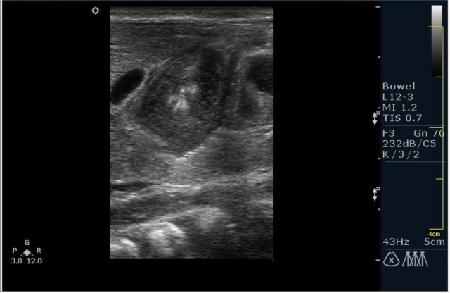

а у нас сегодня опять одна красава! (месяца 3 НИОДНОГО пилоростеноза небыло!)

34647.JPG

34648.JPG

сорри, колесико недотянула